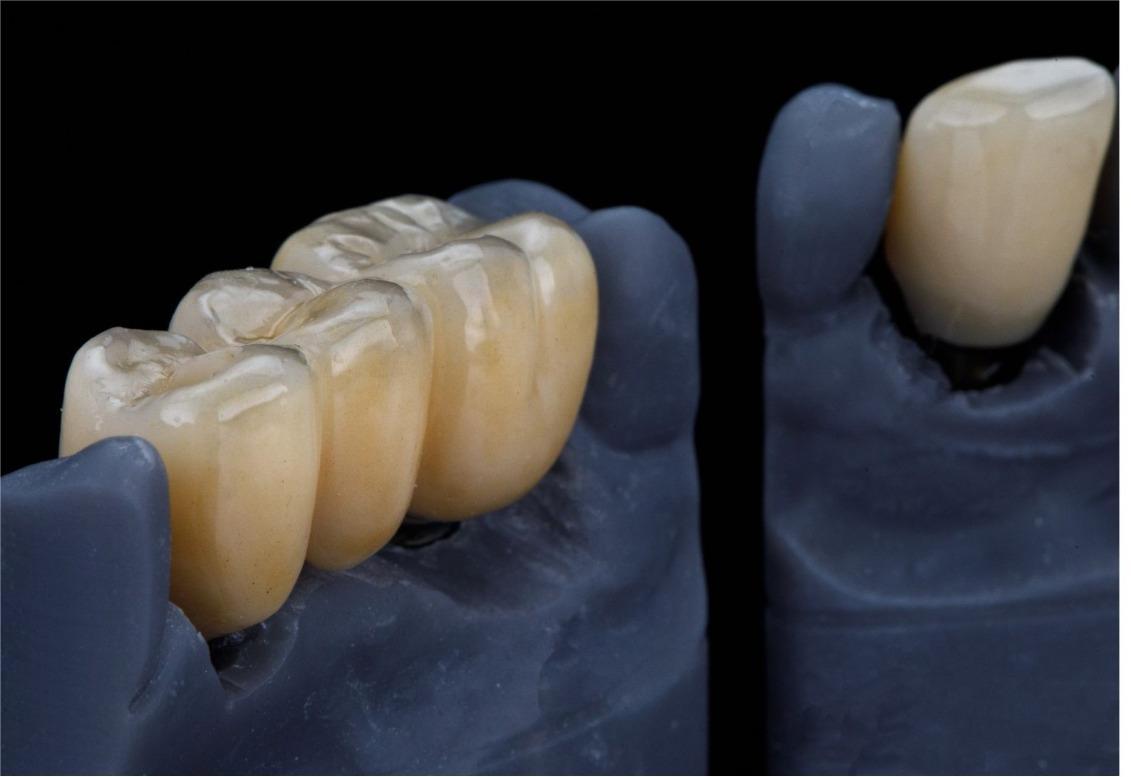

Smile Transformation Journey

Case Highlights. Visible Results